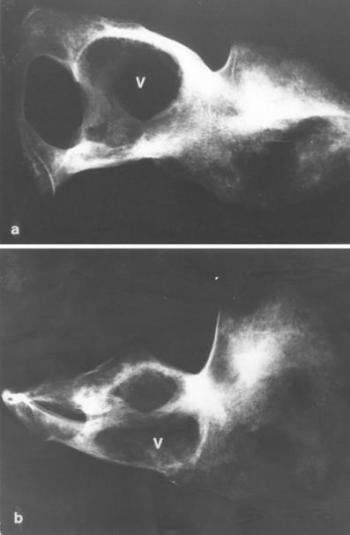

A gennyes arthritis

- Az ízületek gyulladásos és degeneratív elváltozásai